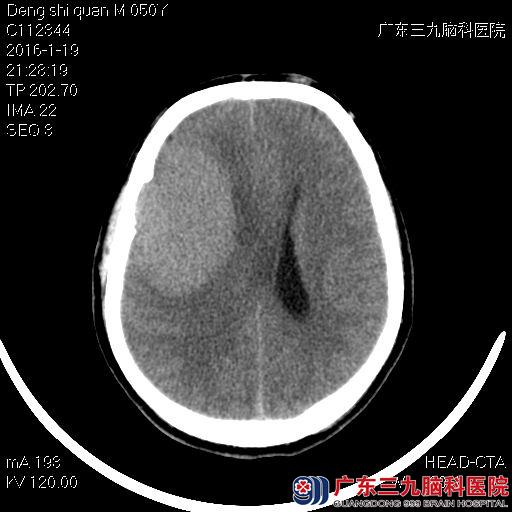

邓先生,49岁,今年一月时,他开始觉得头痛,疼痛持续了十多天都没有缓解,以为自己感冒了,但吃过药后也没有明显的改善。之后头痛的症状逐渐加重,他到当地医院检查了头颅CT,结果提示右侧额颞部巨大占位性病变,医生考虑脑膜瘤可能性较大,为了进一步治疗,邓先生来到广东三九脑科医院。

入院后,神经外七科的吾太华主任安排邓先生检查头颅MRI,结果显示:右侧额颞部大脑凸面占位性病变,考虑为脑膜瘤可能性大,待排血管周细胞瘤。完善了所有术前准备及相关检查后,吾太华主任决定先为其实施肿瘤供血动脉栓塞术,术中栓塞右侧脑膜中动脉其中2条分支。术后第二天,邓先生又接受了右侧额颞部巨大占位性病变切除术,术中肿瘤被完整切除,肿瘤病理结果示:右侧额颞部巨大脑膜瘤(过渡型WHOⅠ级)。

术前图片